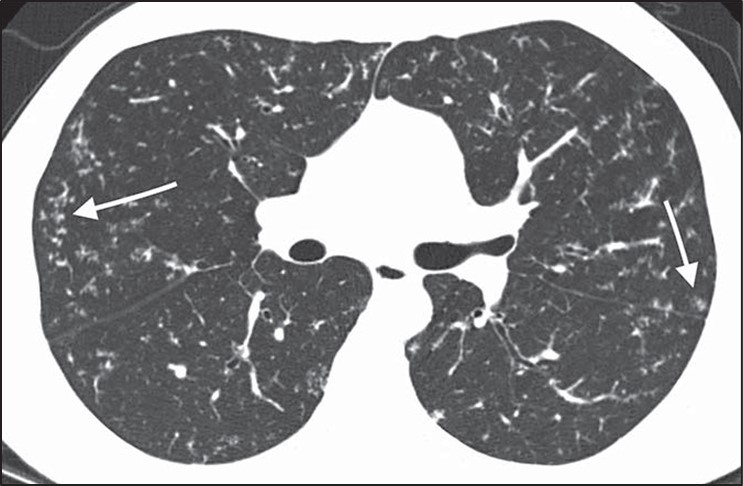

The determination of the predominant pattern of diffuse nodular lung disease has several pitfalls. The perilymphatic pattern shows significant heterogeneity in the distribution of nodules. Although peribronchovascular and subpleural nodules are most typical, nodules in the interlobular septa, which also contain lymphatics, may predominate [26]. These cases may be confused for lymphangitic spread of tumor or pulmonary edema, although the thickening of the interlobular septa in pulmonary edema should be smooth, not nodular. The centrilobular interstitium is continuous with the peribronchovascular interstitium. Rarely, lymphatic diseases may have a predominance of centrilobular nodules overlapping with the centrilobular distribution (Fig. 10).

Fig. 10—Axial high-resolution CT scan shows centrilobular nodules in perilymphatic disease. Many centrilobular nodules (arrows) are present in this patient with sarcoidosis. Subpleural nodules reflect perilymphatic distribution of disease.

Although many centrilobular nodules may be present in lymphatic diseases, nodules should also be seen in the peribronchovascular or sub- pleural interstitium. This is in distinction to the centrilobular pattern in which only centrilobular nodules are present and no subpleural nodules should be seen. Lastly, diseases typically associated with a perilymphatic distribution of nodules (such as sarcoidosis) may occasionally show a fairly homogeneous involvement of the lung, mimicking a random distribution [27] (Fig. 11).